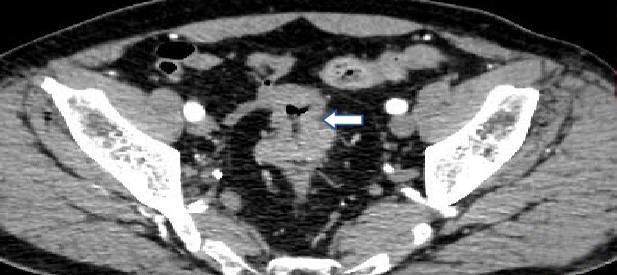

• 计算机体层摄影血管造影在腹腔镜结肠癌根治术前评估中的应用效果

2025, 31(6):24-31. DOI: 10.12235/E20240177

摘要 (181) HTML (147) PDF 4.65 M (171) 评论 (0) 收藏

摘要:目的 分析计算机体层摄影血管造影(CTA)在腹腔镜结肠癌根治术前评估中的应用效果。方法 回顾性分析2021年1月-2024年2月于该院接受腹腔镜结肠癌根治术的120例患者的临床资料。其中,60例行常规腹部CT和CTA,60例行磁共振成像(MRI)。以术后病理为金标准,判断CTA对临床T分期与术后病理的一致性,以及评估肿瘤是否侵犯肠系膜血管和周围组织的准确度。结果 术前CTA诊断T分期的准确率为95.00%(57/60),一致性好(Kappa = 0.925,P < 0.05);术前MRI诊断结肠癌T分期的准确率为98.33%(59/60),两者比较,差异无统计学意义(χ2 = 0.26,P > 0.05)。CTA预判肿瘤是否累及肠系膜上动脉、肠系膜上静脉、肠系膜下动脉、肠系膜下静脉、腹主动脉、肾动脉、肾静脉和脾动脉等血管,与术后病理的一致性好。特别是在预测肠系膜血管受累方面,CTA的敏感度为94.44%,特异度为95.83%,准确度高达95.00%。结论 对于行腹腔镜结肠癌根治术的患者,术前CTA不仅能清晰地显示结肠癌T分期,还能揭示肠系膜血管的走行和变异,以及肿瘤与周围组织的关系和侵犯程度,从而为手术规划提供强有力的支持,确保了腹腔镜手术的安全性,减少了不必要的手术风险。